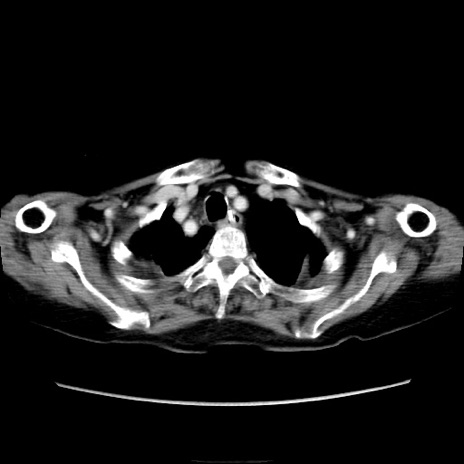

症例40(横断像)

【症例】90歳代女性

【主訴】腹痛・嘔吐

【現病歴】 食欲低下、嘔吐があり昨日他院受診。肺炎と診断され入院となる。入院後より腹部全体に圧痛あり。胃管留置され経過みていたが、症状持続するため、

当院転院となる。

【既往歴】胸椎圧迫骨折、胆石症

【身体所見】腹部:中央に激痛あり、圧痛あり、反跳痛不明

【データ】WBC 17100、CRP 18.82

横断像